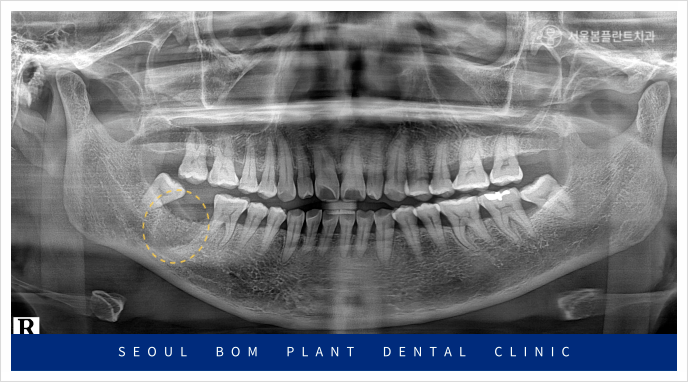

이 환자분의 상태를 정밀하게 검사하기 위해

파노라마 촬영을 진행한 결과,

아래턱 오른쪽 두 번째 어금니(#47) 주변에

심각한 염증이 확인되었습니다.

이 염증이 하치조 신경관까지 영향을 미쳐,

방치할 경우 주변 조직과 다른 치아에까지

영향을 미칠 수 있는 위험한 상황이었습니다.

따라서 이 환자분에게는 빠른 발치가

필요한 상황이었습니다.

뼈이식 2달 후, 파노라마 촬영을 통해

발치 부위에 하얗게 뼈가 차오른 것을 확인한 후,

임플란트 식립을 진행하였습니다.

오금역치과 서울봄플란트에서는 임플란트 식립 전,

파노라마와 3D CT 촬영을 통해 환자의

구강 상태를 꼼꼼하게 검진했습니다.